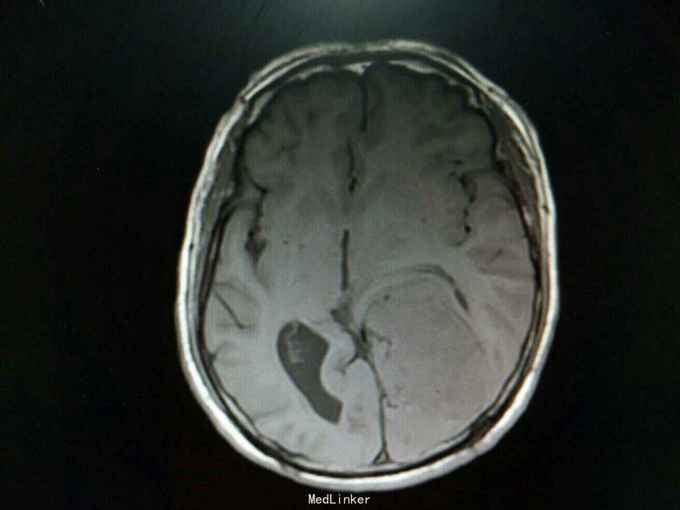

查体:生命体征平稳,神经系统检查未见明显异常。辅助检查:头颅增强+血管MR扫描提示:双侧额顶叶、侧脑室周围见斑片状异常信号区,T1WI呈等信号,T2WI及T2-FLAIR呈稍高信号。左侧枕部大脑镰旁可见团状软组织肿块影,边界清,形态不规则,呈分叶状,大小约62mm×49mm。病灶T1WI呈等信号,T2WI呈稍低信号,周围可见脑脊液环绕;增强扫描病灶明显均匀强化。病灶占位效应较明显,左侧顶枕叶脑实质受压向内移位,左侧侧脑室受压变形。中线结构稍向右移位。余脑实质未见异常信号灶。颅骨未见明确异常。头颅MRA:病灶内可见多发迂曲血管影,可见大脑后动脉及脑膜动脉供血。双侧大脑前、中、后动脉管壁光滑,走行自然,管腔未见明显扩张或狭窄,未见动脉瘤征象。Willis环未见异常。1. 左侧枕部大脑镰旁占位性病变,考虑脑膜瘤可能性大;2. 轻度脑白质疏松;2. 头颅MRA提示病灶血供来自左侧大脑后动脉及脑膜动脉;余未见异常。

诊断:左枕部大脑镰旁脑膜瘤 处理:左枕部开颅大脑镰旁脑膜瘤切除术

术后病理提示:(左顶枕叶肿瘤)脑膜瘤,上皮型,WHOⅠ级。大脑镰旁脑膜瘤是指位于大脑纵裂并与大脑镰相连的一类临床上常见的脑膜瘤,常突入一侧大脑半球内,有时可向双侧发展。也有少数肿瘤呈扁平型,在大脑镰内浸润性生长。肿瘤可由大脑镰脑膜动脉供血,也可由脑内动脉供血,其前部可来自眼动脉分支,后部来自枕动脉,中部可有脑膜中动脉供血。在肿瘤基底和附近的大脑镰内有多条扩张的静脉。